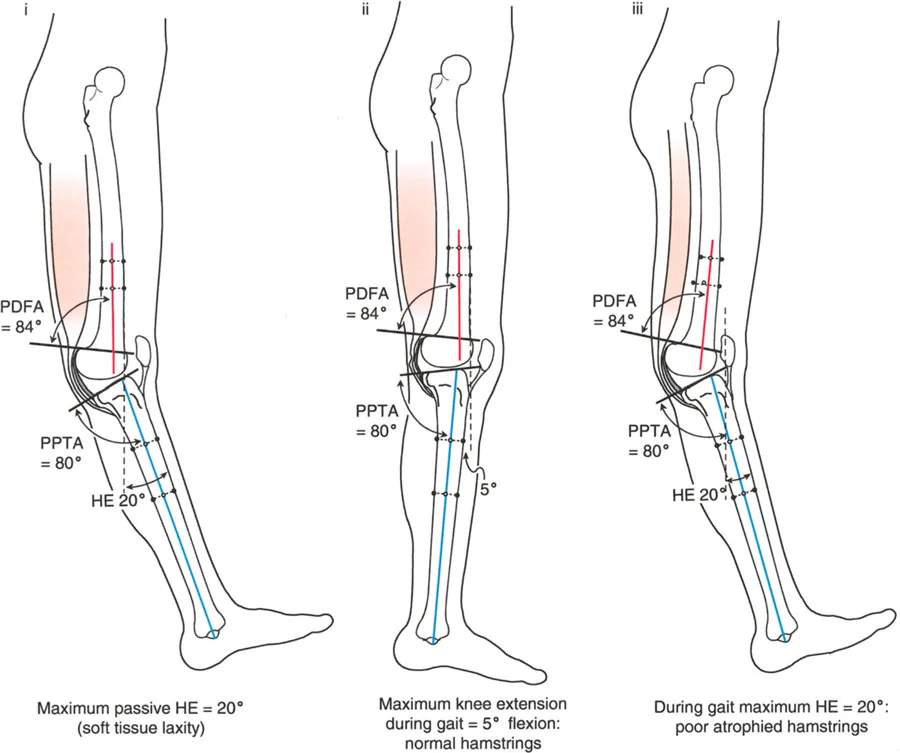

- الأشعة الجانبية الطويلة للطرف السفلي بالكامل أثناء الوقوف في أقصى بسط (Standing Long-Leg Lateral View in Maximum Extension): تُستخدم لتقييم تحدد حركة الركبة (FFD) والركبة الارتدادية (Recurvatum)، وتحديد ما إذا كان التشوه عظميًا أو ناتجًا عن تقلص في الأنسجة الرخوة.

تحدُّد حركة الركبة هو عدم القدرة على مد الركبة بالكامل. يمكن أن يكون سببه عظميًا أو ناتجًا عن تقلص في الأنسجة الرخوة.

- التشخيص الدقيق: يجب تحديد ما إذا كان تحدد الحركة ناتجًا عن تشوه عظمي (تقوس أمامي في الفخذ أو الساق) أو تقلص في الأنسجة الرخوة (الأوتار الخلفية، محفظة المفصل).

الركبة الارتدادية هي فرط البسط في الركبة. غالبًا ما تكون غير مصحوبة بأعراض في الأشخاص ذوي العضلات السليمة، ولكنها قد تسبب مشاكل في حالات ضعف العضلات أو التشوهات العظمية.

- التشخيص: يجب تحديد ما إذا كانت الارتدادية عظمية (تقوس خلفي في الفخذ أو الساق) أو ناتجة عن رخاوة في الأنسجة الرخوة أو ضعف عضلي.